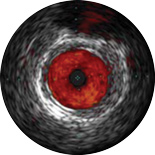

ChromaFlo обеспечивает простую оценку аппозиции стента, размера просвета сосуда и других параметров за счет выделения кровотока красным цветом на изображении в одно нажатие кнопки. Функция ChromaFlo доступна на системах для интервенционных вмешательств Philips.

Эта функция создана для быстрой оценки размера просвета сосуда и аппозиции стента; она облегчает определение ветвей сосудов, диссекций и тромбов, а также упрощает оценку распределения бляшек в области бифуркаций. Функция ChromaFlo выделяет кровоток красным цветом, что помогает:

Во время визуализации не требуется выполнять промывание или какие-либо специальные процедуры. Просто активируйте функцию ChromaFlo одним нажатием кнопки.

Функция ChromaFlo совместима с цифровыми катетерами для ВСУЗИ Philips Eagle Eye Platinum.